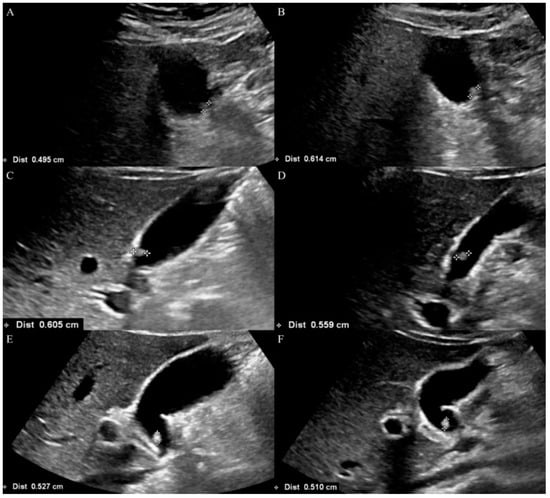

2.2. Image Acquisition of GB Polyps